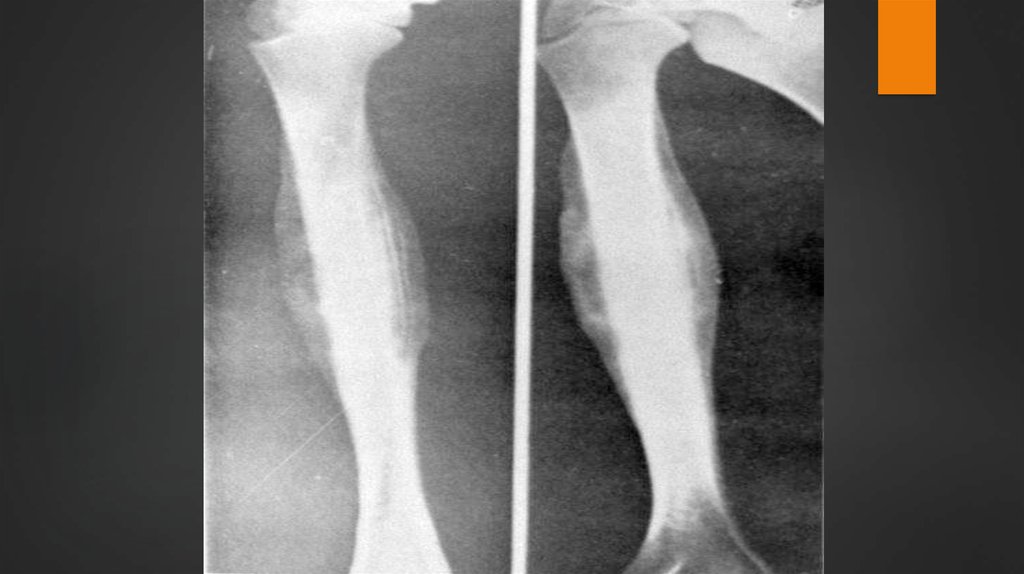

Изменения

в костях зависят от вида

остеогенной саркомы, который

определяет рентгенологическую

картину.

6. Виды остеогенной саркомы:

Остелитическая

Остеобластическая

Смешанные

формы